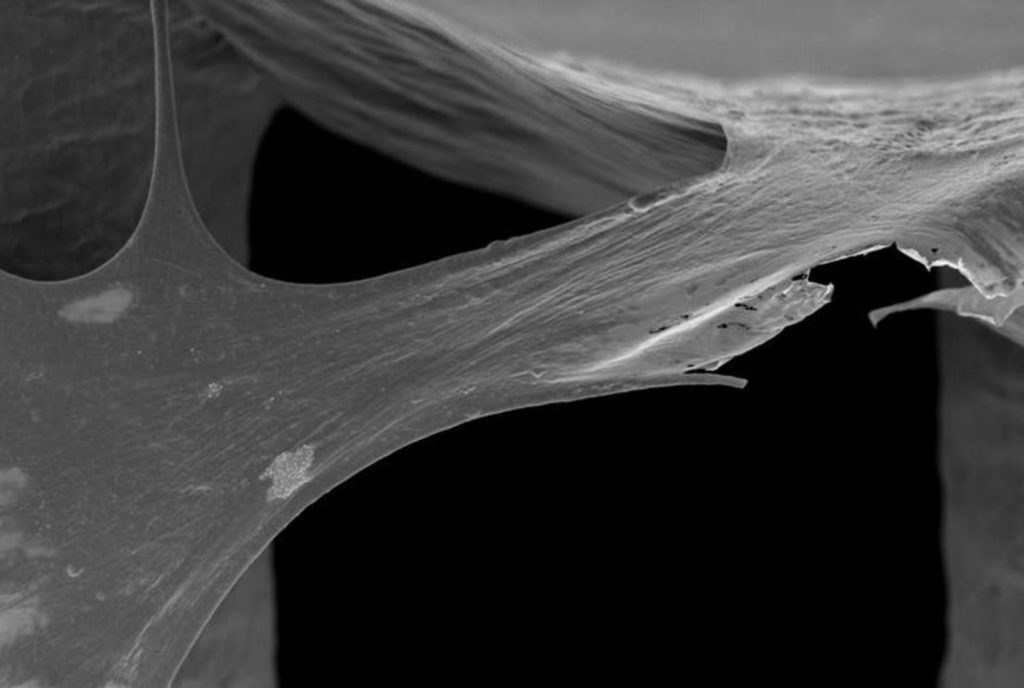

This is where the newly conceived 3D-printed bone bricks come in. The treatment uses medical scaffolds made of polymer and ceramic materials, which can be clicked together to create a temporary structure that perfectly fills the bone gap caused by the blast injury. These bone bricks would have all the support of a normal bone in compression, while inducing the formation of new bone tissue around the structure. As the bone regenerates, the bricks dissolve. Each of these degradable bricks has pores containing antibiotic ceramic paste, which combats infection in a remarkably practical way during the healing period.